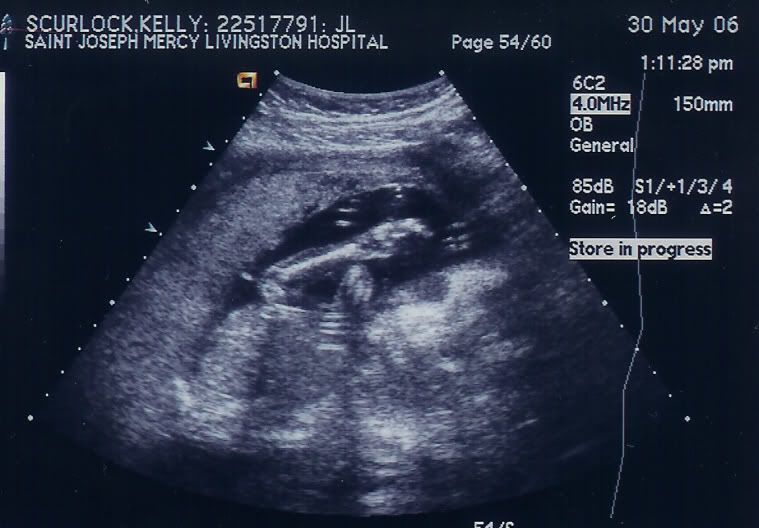

i had my ultrasound today...it's a boy.....hahaha hi saw it's lil ******

it was pretty cool. they messured all the bones, and i saw its brain....here's the ultrasound pics....he he he its waving in one of them...i think it looks like a lil alien.

speede- yeah those are his eyes....super creapy huh? his legs are there you just can't see them. b/c of where she had the hand piece to the ultrasound machine.